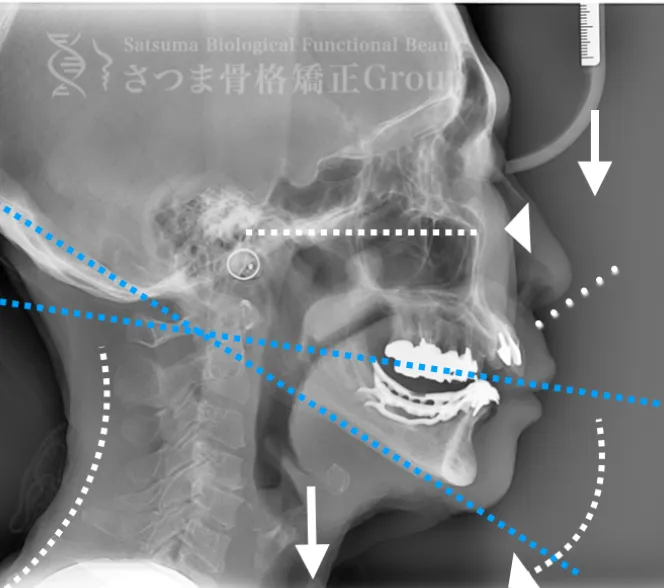

渋谷TMJ歯科クリニックでは、頭蓋および頸椎の歪みが顎位(あごの位置)と咬合(噛み合わせ)の乱れを引き起こし、その結果として顔の歪み、顎関節症、食いしばり、ストレートネックによる強い肩こり、さらには自律神経の乱れへとつながると考えています。

これらの問題を正確に評価するため、当院では セファロシステムによるレントゲン撮影(X-ray images) を行っています。

セファロ撮影によって 顎関節・頭蓋骨・頸椎の位置関係を客観的に可視化でき、施術前の状態を科学的に把握することが可能となります。

施術の前後で撮影したレントゲン写真を比較することで、改善の度合いや変化を一目で確認できます。